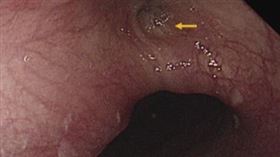

咳嗽竟噴出石頭 男子食道被結石「鑿洞」

一名60多歲男性,從事石雕工作達20~30年,長期有...